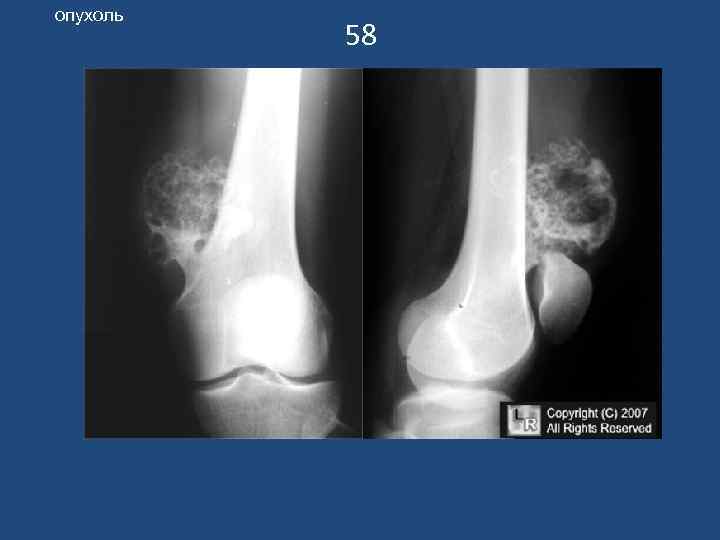

опухоль 58